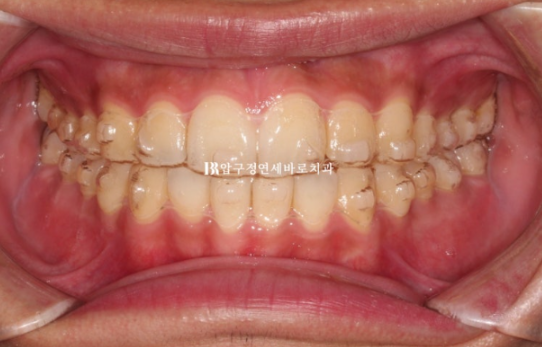

24.06

14개 첫세트의 장치를 다 낀 후 모습입니다.

앞니 높낮이가 여전히 아쉽습니다.

배열도 가지런해졌고 이소맹출이 되어서 입천장으로 들어가있던 치아도 제자리를 찾았습니다.

이 부분 해결을 위해 고무줄 처방이 있었습니다.

사진상 금속 고리끼리 고무줄을 겁니다.

배열, 앞니 높낮이 등등 추가로 개선할 부분들이 있어서 추가제작을 하기로 했습니다.